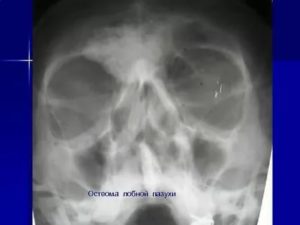

Подозрение на развитие патологического процесса возникает во время пальпации. Чтобы подтвердить или опровергнуть предположение, назначается рентгенография пораженной части. Это основной способ проведения диагностики.

Рентген осуществляется в двух проекциях. Позволяет установить имеющиеся разрушения кости, а также выявить наличие плотного и губчатого образования за ее пределами. В том случае, когда опухоль имеет незначительные размеры, рентгенография оказывается малоэффективной.

Основной диагностической процедурой считается рентгенография, при которой в области поражения идентифицируется равномерное затемнение с нечеткими краями.

Для выяснения точного расположения опухоли, как правило, осуществляется серия рентгеновских снимков под разным углом.

Основной способ диагностики – рентгенография. На снимке это будет выглядеть как однородная по структуре округлая опухоль с четкими границами. Остеоидная остеома на снимке представляет собой нечеткий дефект – очаг деструкции.

- Рентгенография позволяет узнать: месторасположение остеомы в кости, строение опухоле, степень деструкции кости, на которой находится новообразование, – а также определить, единичная опухоль или это множественное разрастание.

Основным методом, позволяющим обнаружить любую опухоль кости, в том числе, остеому, является рентгенография. Если новообразование расположено глубоко в тканях головы, имеет небольшой размер, поражает кости черепа с внутренней стороны, то целесообразнее произвести компьютерную томографию, дающую больший объем информации относительно его размеров и месторасположения.